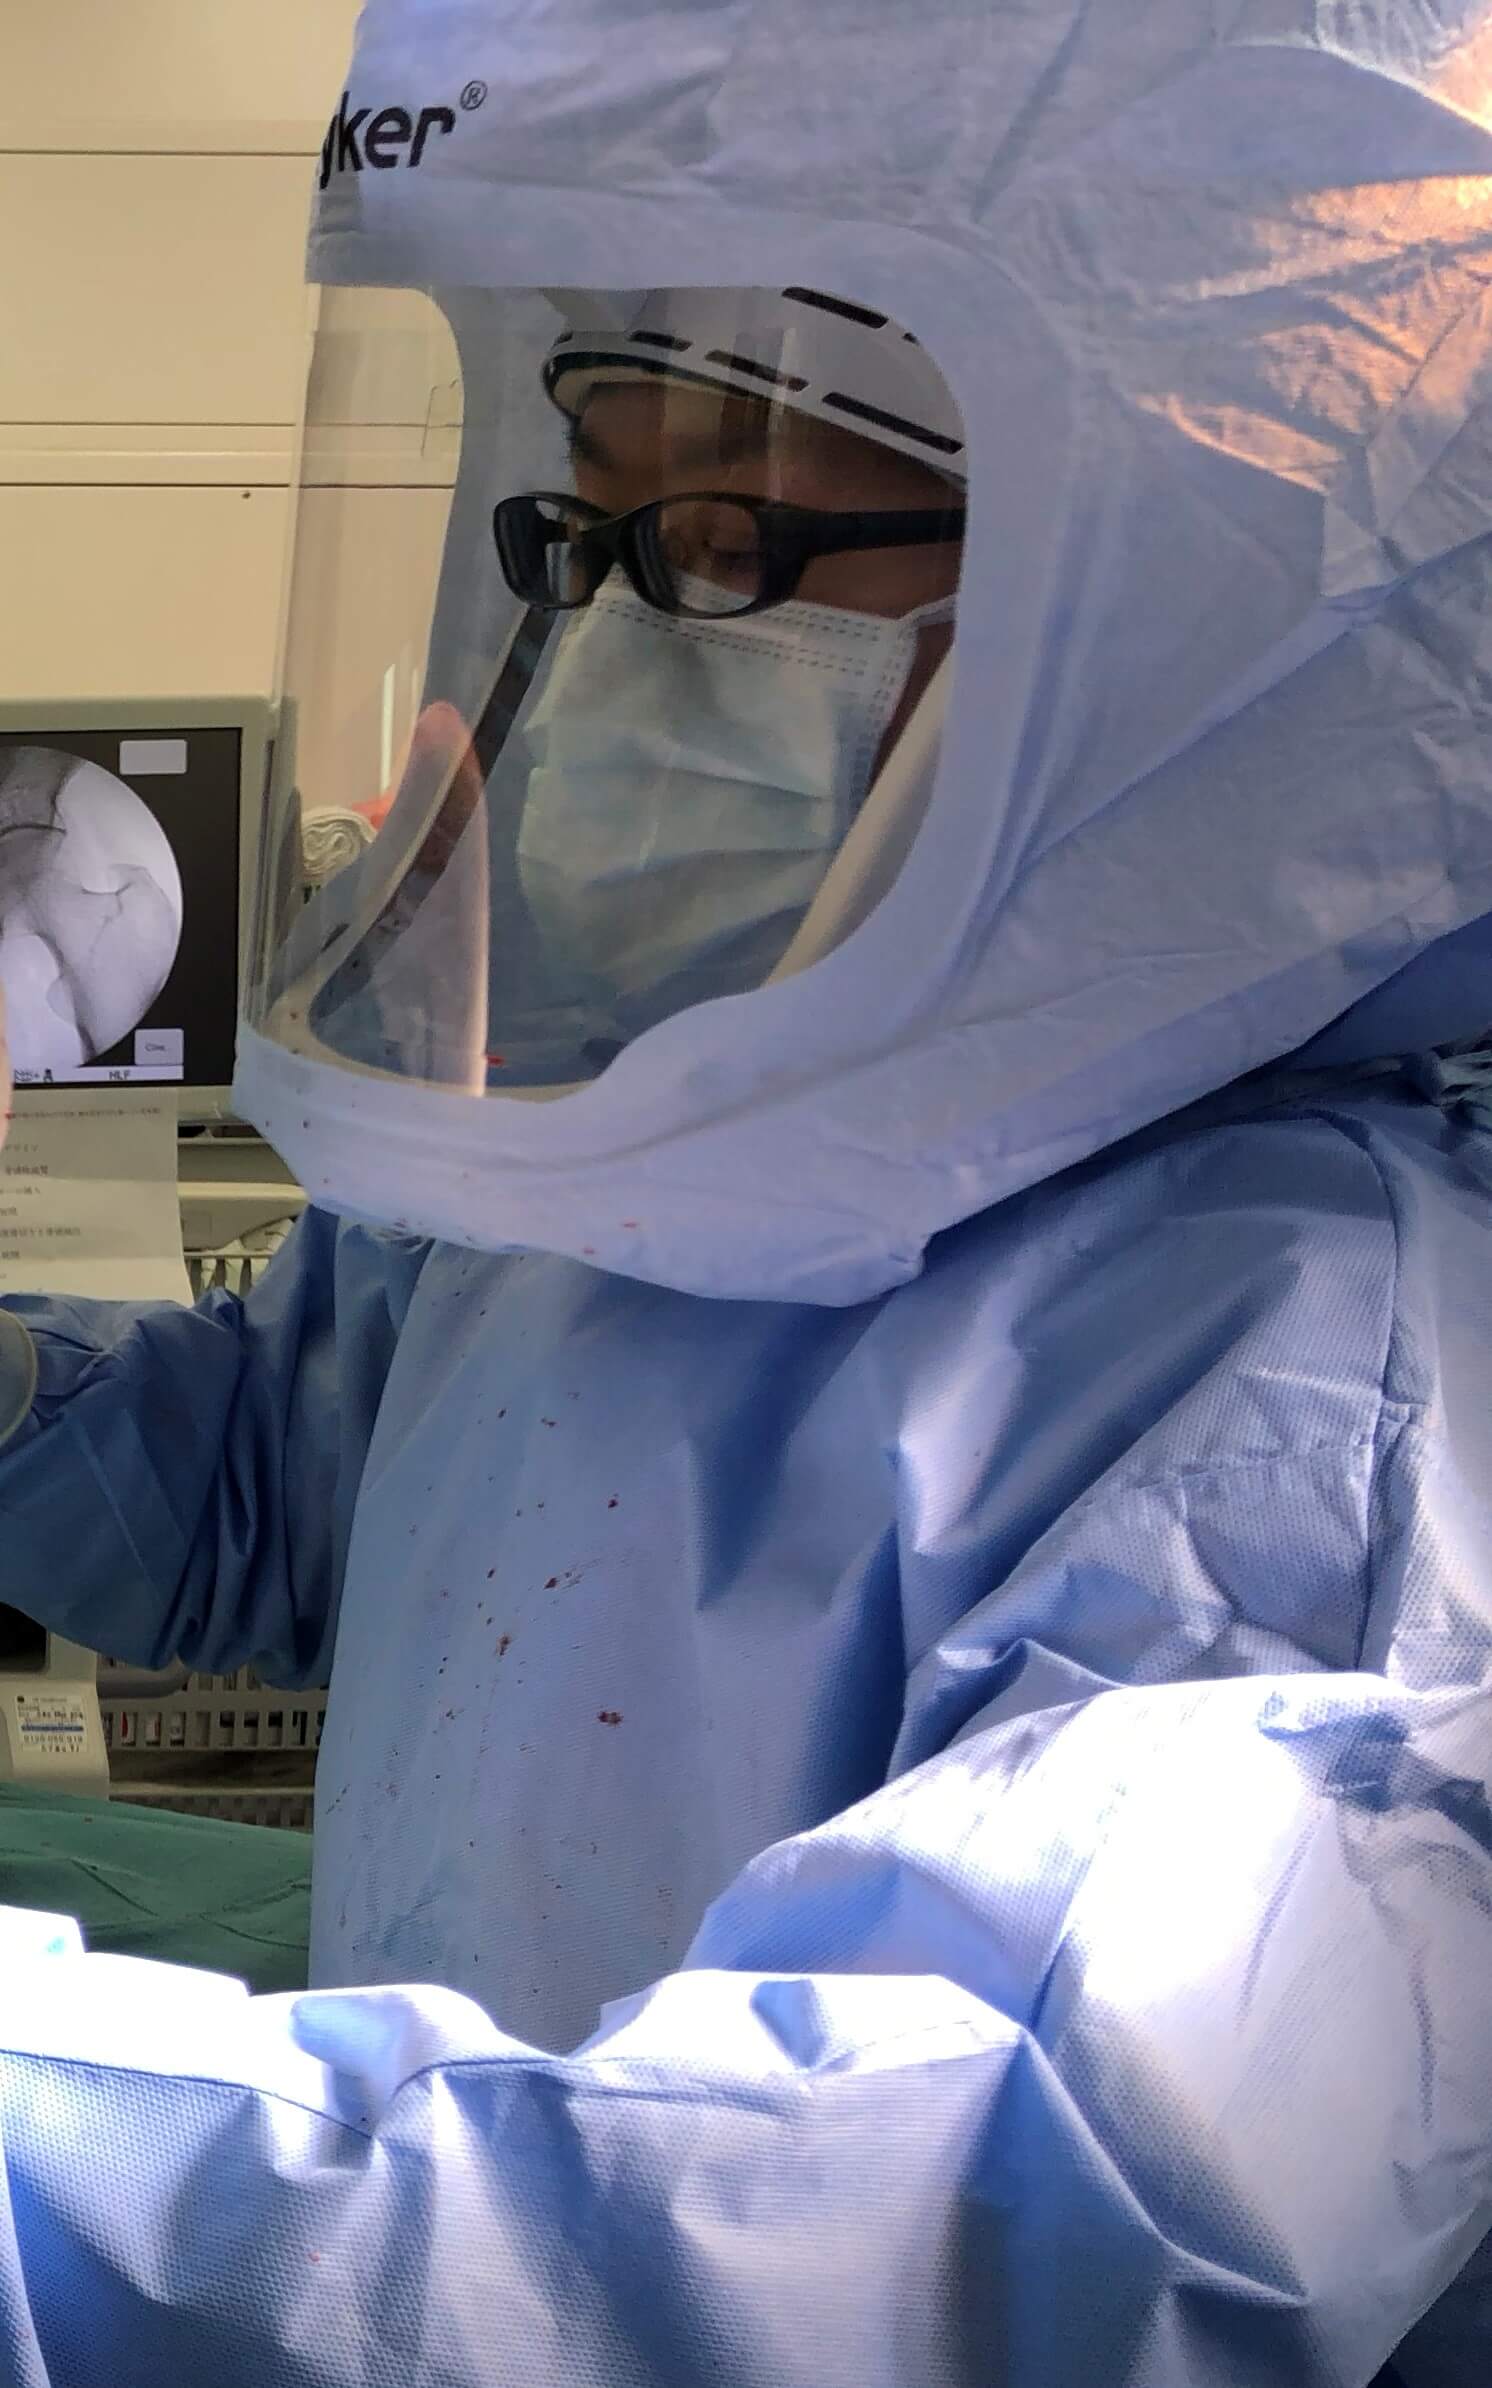

もちろん手術における侵襲を少しでも小さくすることも

とても大事な要素になります。

膝が腫れないように

少しでも気を使いながらこれからも手術をしていきたいと思います。